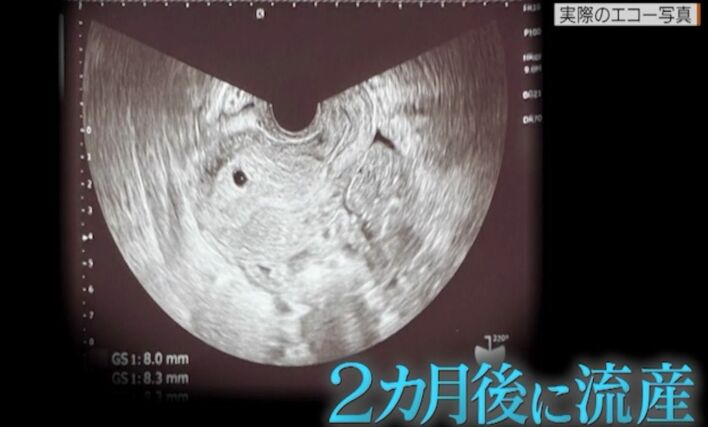

岡副麻希の第1子出産は計画出産の予定が3日目の朝に帝王切開を決断 最愛の母を失って1年…母の思いを受け止めた娘が「母」になるまで